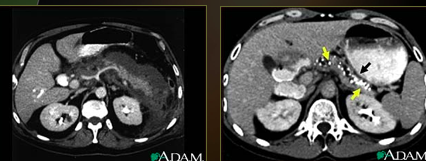

What is this image showing?

Pancreatitis

Left image: upper abdominal CT scan shows inflammation and swelling of the pancreas. Consistent with acute pancreatitis.

Right image: CT scan of the upper abdomen showing multiple white-colored calcifications. These occur in chronic pancreatitis.